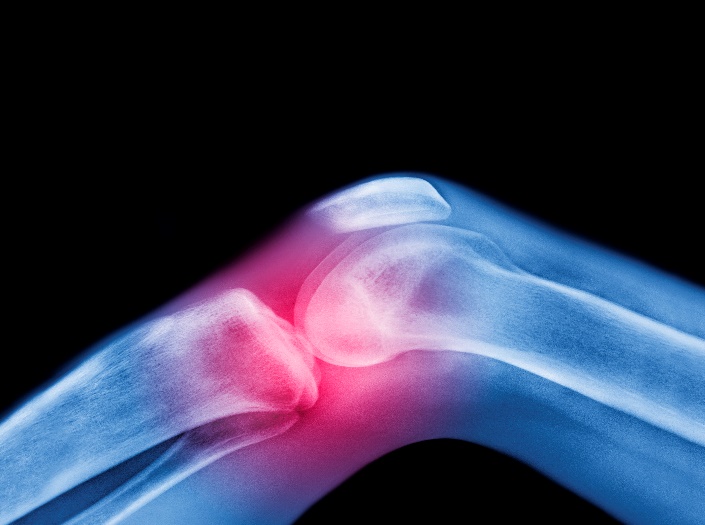

骨質疏鬆症為一種全身骨骼慢性疾病,由於骨質減少,骨骼孔隙變大且疏鬆,導致骨頭脆弱易斷,因而增加骨折風險,為全球僅次於癌症之第二大疾病。

(圖片來源:Getty)